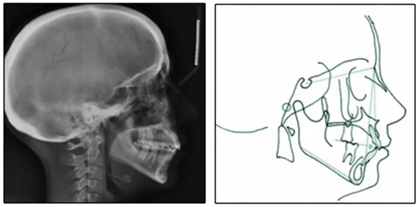

患者是一名39歲的白人婦女,病史不明。她主訴是她的右側(cè)顳下關(guān)節(jié)有不適癥狀,并希望改善她的笑容。她有一個對稱的臉型和一個II類2分類的微笑。她的側(cè)貌是凸的,90°的鼻唇角和骨性下頜骨發(fā)育不足??趦?nèi),上頜中線與面部重合,但下頜中線向右側(cè)偏移5mm;存在6mm的深覆蓋。她的兩側(cè)都是I類磨牙關(guān)系,左側(cè)是I類尖牙關(guān)系,右側(cè)是完全的II類尖牙關(guān)系。下頜右側(cè)第二前磨牙先天性缺失(圖1和圖2)。最初的全景片顯示了足夠的骨質(zhì)水平和全部的第三磨牙(圖3)。治療前的頭影測量片片和相應(yīng)的頭影測量圖(圖3)證實ANB為7°,Wits評估為6 mm的骨性II類錯合(表)。上頜切牙相對與面部和顱底的位置很好。下頜切牙前傾。診斷為II類2分類錯合畸形,伴有骨性下頜發(fā)育不足,右側(cè)顳下頜關(guān)節(jié)癥狀,下頜中線向右側(cè)偏移5mm,先天性右下第二前磨牙缺失。

圖3. 治療前頭影側(cè)位片,頭影測量描跡圖和全口X光片